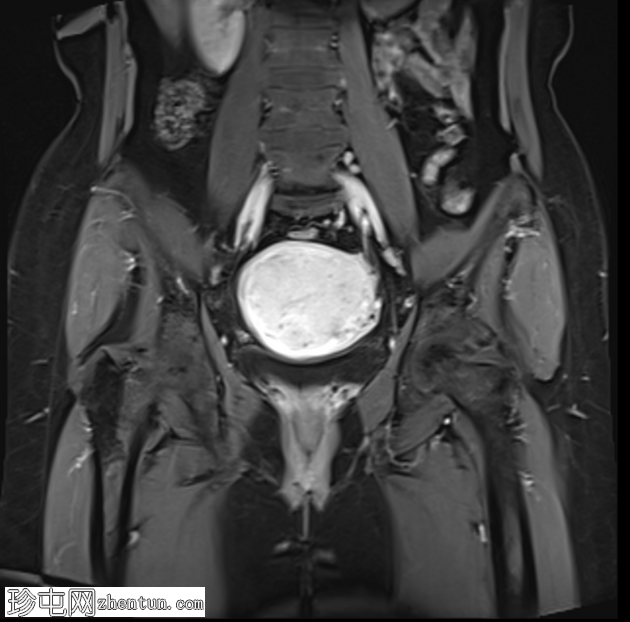

冠状位T1加权像(增强)

脂肪抑制像(振动成像)

子宫增大,交界区弥漫性增厚,厚度约2.5 cm,边界模糊,在T1加权像和T2加权像上均可见无数点状高信号灶,提示出血灶。

在预期的膀胱尿道区域可见一小片异常信号强度的局灶性区域,T2加权像呈高信号,提示膀胱尿道子宫内膜异位症。